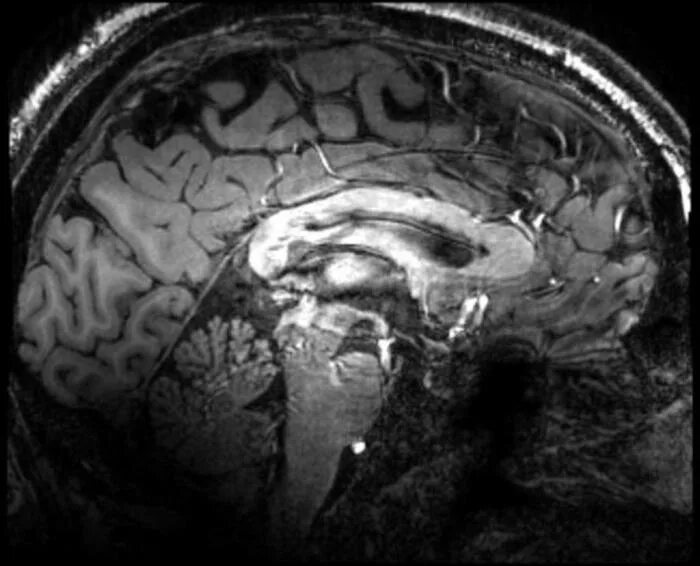

Симптомы атеросклероза головного мозга у женщин